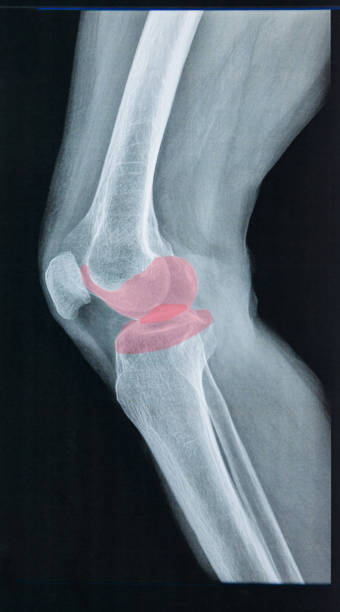

무릎 연골 손상 증상은 이미 연골이 찢어지고 부러진 경우 통증이 너무 크기 때문에 무릎을 구부리거나 펴거나 제대로 기능하지 못하는 경우가 돼서야 인식하는 경우가 많습니다. 이 경우 연골에 염증이 생기고 증상이 너무 심해 병원에 가서 진찰을 받아야하며 정확한 검사 없이는 정확한 진단이 불가능하고 적절한 치료를 받을 수 없기 때문에 준비를 잘 하셔야 합니다.

무릎 연골 손상은 무릎 관절을 사용하여 움직일 때도 통증을 유발할 수 있습니다. 통증은 무릎 연골의 파열로 인해 발생하는 가장 흔한 통증으로 걷거나 계단을 내려갈 때 또는 내리막길에서 통증을 경험할 수 있어 빠른 치료가 요구됩니다.